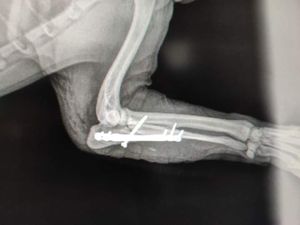

O Bob é um cachorro doméstico e não tem costume de andar na rua sem o tutor,mas infelizmente ele acabou fugindo e foi atropelado.

Ele está com uma fratura nas patinhas e precisará passar por cirurgia, abaixo segue o orçamento para comprovação.